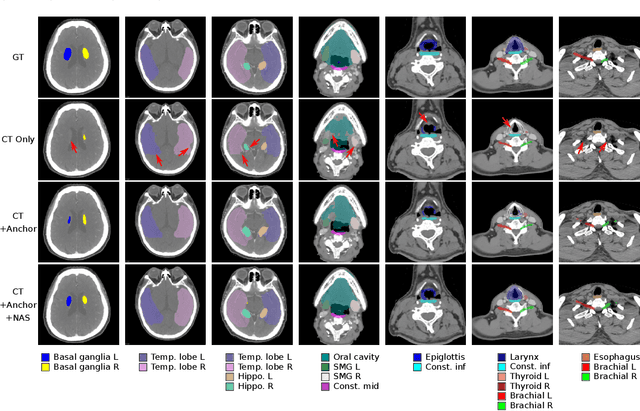

Abstract:Accurate organ at risk (OAR) segmentation is critical to reduce the radiotherapy post-treatment complications. Consensus guidelines recommend a set of more than 40 OARs in the head and neck (H&N) region, however, due to the predictable prohibitive labor-cost of this task, most institutions choose a substantially simplified protocol by delineating a smaller subset of OARs and neglecting the dose distributions associated with other OARs. In this work we propose a novel, automated and highly effective stratified OAR segmentation (SOARS) system using deep learning to precisely delineate a comprehensive set of 42 H&N OARs. SOARS stratifies 42 OARs into anchor, mid-level, and small & hard subcategories, with specifically derived neural network architectures for each category by neural architecture search (NAS) principles. We built SOARS models using 176 training patients in an internal institution and independently evaluated on 1327 external patients across six different institutions. It consistently outperformed other state-of-the-art methods by at least 3-5% in Dice score for each institutional evaluation (up to 36% relative error reduction in other metrics). More importantly, extensive multi-user studies evidently demonstrated that 98% of the SOARS predictions need only very minor or no revisions for direct clinical acceptance (saving 90% radiation oncologists workload), and their segmentation and dosimetric accuracy are within or smaller than the inter-user variation. These findings confirmed the strong clinical applicability of SOARS for the OAR delineation process in H&N cancer radiotherapy workflows, with improved efficiency, comprehensiveness, and quality.

Abstract:OAR segmentation is a critical step in radiotherapy of head and neck (H&N) cancer, where inconsistencies across radiation oncologists and prohibitive labor costs motivate automated approaches. However, leading methods using standard fully convolutional network workflows that are challenged when the number of OARs becomes large, e.g. > 40. For such scenarios, insights can be gained from the stratification approaches seen in manual clinical OAR delineation. This is the goal of our work, where we introduce stratified organ at risk segmentation (SOARS), an approach that stratifies OARs into anchor, mid-level, and small & hard (S&H) categories. SOARS stratifies across two dimensions. The first dimension is that distinct processing pipelines are used for each OAR category. In particular, inspired by clinical practices, anchor OARs are used to guide the mid-level and S&H categories. The second dimension is that distinct network architectures are used to manage the significant contrast, size, and anatomy variations between different OARs. We use differentiable neural architecture search (NAS), allowing the network to choose among 2D, 3D or Pseudo-3D convolutions. Extensive 4-fold cross-validation on 142 H&N cancer patients with 42 manually labeled OARs, the most comprehensive OAR dataset to date, demonstrates that both pipeline- and NAS-stratification significantly improves quantitative performance over the state-of-the-art (from 69.52% to 73.68% in absolute Dice scores). Thus, SOARS provides a powerful and principled means to manage the highly complex segmentation space of OARs.